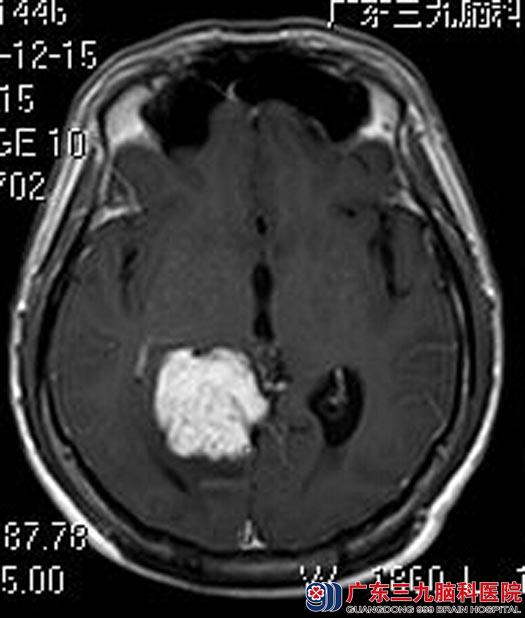

进一步头颅MR检查提示:右侧颞枕部内侧(小脑天幕上、下)示一团块状占位性病变,大小约4.29cm×4.18cm×4.51cm;头颅CTA检查提示:右侧颞枕部内侧(小脑天幕上、下)占位性病变,血供丰富、内示多发细小血管影,双侧大脑后动脉分支包绕病变(右侧为主),考虑脑膜瘤。由于肿瘤血供丰富,经讨论,术前行肿瘤部分供血血管栓塞术,术中栓塞左侧大脑后动脉远端、左侧大脑上动脉分支远端。次日,由鲁明主任主刀在全麻下行经popen入路松果体脑膜瘤切除术,术中见灰白色肿瘤组织,跨小脑幕,血供丰富,边界清晰,予显微镜下逐步分离分块切除,右侧大脑后动脉P3段、右侧小脑上动脉分支主要参与肿瘤供血,予动脉瘤夹肿瘤基底部位于小脑幕,肿瘤镜下全切。术后林先生恢复很好。病理结果:皮细胞型脑膜瘤(WHO I级)。

手术前